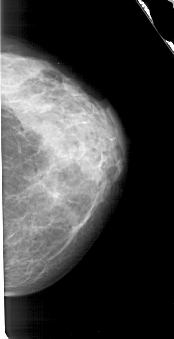

A_1888_1.RIGHT_CC

RIGHT_CC LINES 4741 PIXELS_PER_LINE 2431 BITS_PER_PIXEL 12 RESOLUTION 43.5 NON_OVERLAY